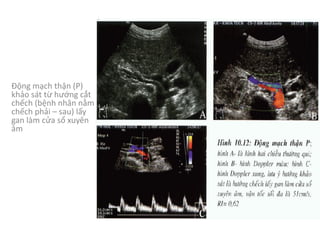

HỆ THỐNG MẠCH MÁU

CHI PHỐI THẬN

- Động mạch thận (P)	xuất phát từ hướng

trước bên (10	giờ),	động mạch thận (T)	xuất

phát từ hướng sau bên (4	giờ),	ngay dưới vị

trí xuất phát của động mạch mạc treo tràng

trên 1	cm

- Thân động mạch thận chạy ra sau và hướng

về rốn thận

Động mạch thận (P)

khảo sát từ hướng cắt

chếch (bệnh nhân nằm

chếch phải – sau)	lấy

gan làm cửa sổ xuyên

âm

- Động mạch thận

(P)	khảo sát từ

hướng cắt chếch

(bệnh nhân nằm

chếch trái – sau)

- Để đầu dò theo

hướng cắt vành

động mạch chủ

bụng thì sẽ nhận

được hình hai

động mạch thận

cùng một lúc

- Các tĩnh mạch được khảo sát từ cùng hướng của động mạch

cùng tên,	thường có khẩu kính lớn hơn động mạch và chạy phía

trước động mạch thận cùng tên.

- Tĩnh mạch thận (T)	trước khi đổ vào tĩnh mạch chủ dưới thì

chui ngang qua	“gọng kìm”	động mạch mạc treo tràng trên và

động mạch chủ bụng thì khẩu kính có giãn lớn hơn